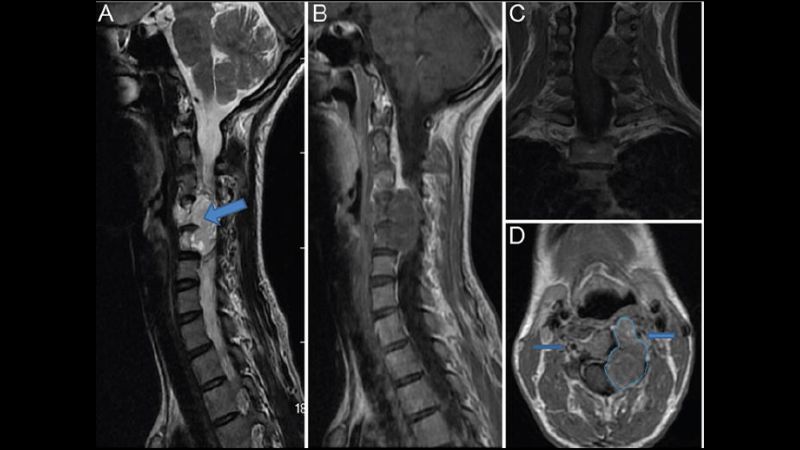

Trên thực tế, u máu cột sống được xếp vào một trong số các bệnh lành tính. Tất nhiên, chúng ta cũng không thể vì thế mà chủ quan với bệnh lý này. Bởi u máu phát triển lớn về kích thước sẽ khiến xương khớp và hệ thần kinh bị ảnh hưởng.

U máu cột sống có thể gây ra nhiều vấn đề sức khoẻ nghiêm trọng